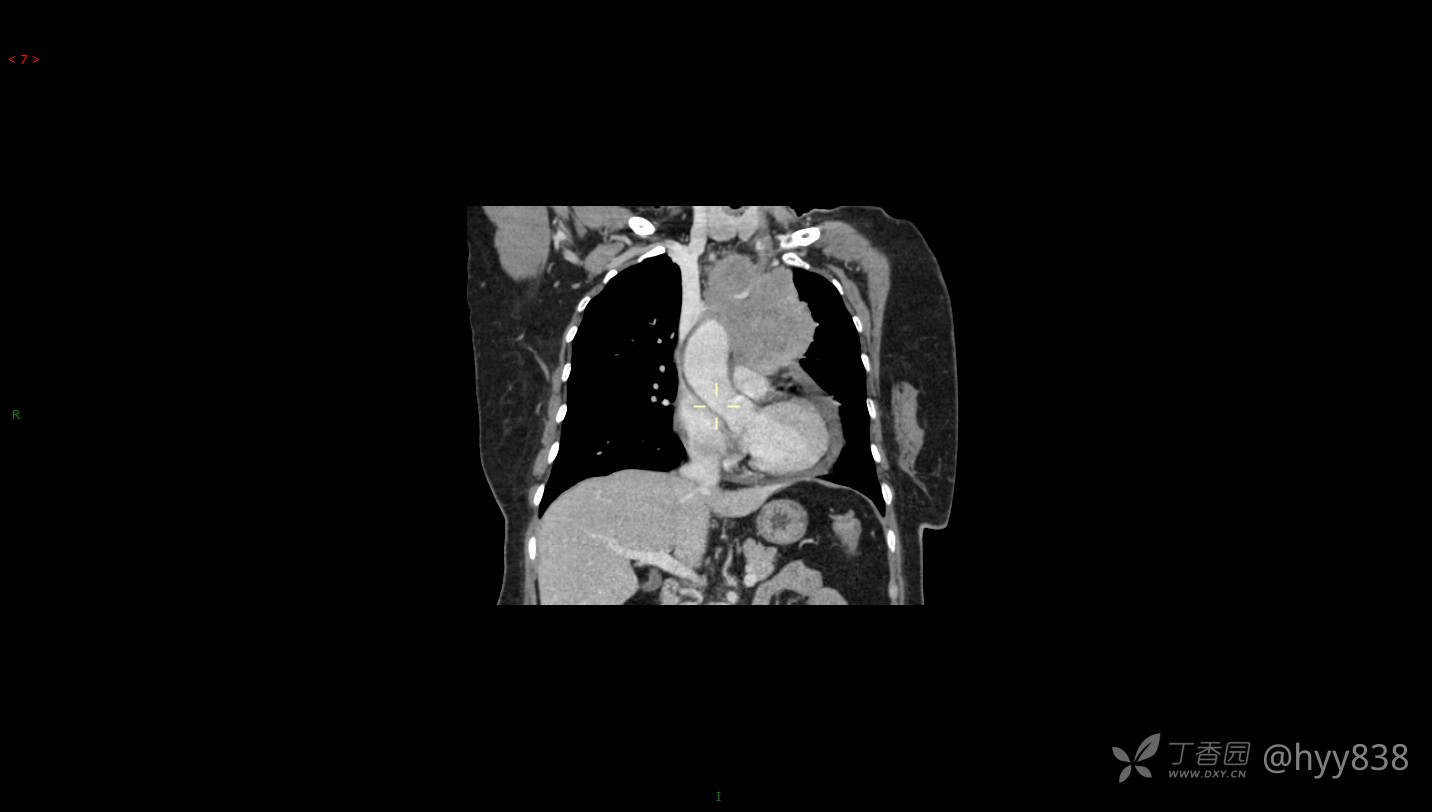

简要病史:患者诉3月余前患新冠肺炎,出现持续性胸闷,活动后可缓解,无胸前区压榨感,无畏寒发热不适,无胸痛咯血、呼吸困难,无恶心、呕吐,无腹痛、腹胀、腹泻等不适,未予以重视,未行特殊处理。患者胸闷持续存在,为进一步诊治,3天前于本院查胸部CT提示前纵膈团块状软组织密度影,肿瘤性病变可能,心包积液,左上肺磨玻璃结节,右下肺增殖灶可能建议进一步检查。门诊以“前纵膈占位” 收入我科。 患者本次起病来精神、食欲、睡眠尚可,大小便正常,体力、体重无明显变化。

辅助检查:CT

临床诊断:纵隔占位

讨论:病变性质?